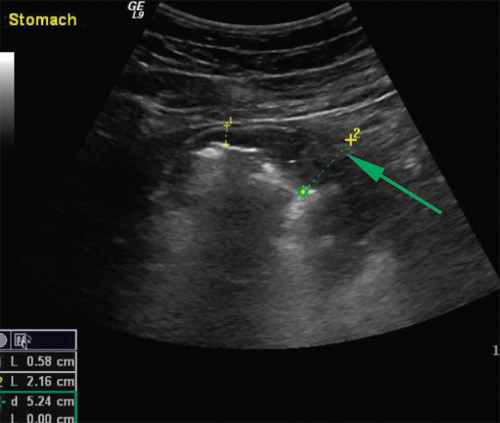

Det ble utført en gastroenterologisk ultralydundersøkelse. Denne viste små mengder ascites og lett forstørret milt. Det mest påfallende funnet var imidlertid betydelig fortykket og foldet ventrikkelslimhinne, målt tykkelse var opp mot 2 cm (fig 1).

Pasienten fikk intravenøs behandling med ganciklovir i 14 dager, så overgang til peroral valaciklovir i fem uker. I tillegg fikk han albumin intravenøst – 40 g/dag – i en uke. Han fikk også diuretika for å mobilisere væske. Som følge av dette regimet gikk ødemene raskt tilbake og vekten ble normalisert. 14 dager etter oppstart av antiviral behandling ble det utført endoskopisk ultralydundersøkelse av ventrikkelen (fig 3a). Det var fortsatt forandringer, men man fikk inntrykk av tilbakegang. Ultralydbildet viste betydelig foldet og fortykket slimhinne, men tykkelsen ble nå målt til ca. 10 mm. Kapselendoskopi viste injiserte slimhinner i ventrikkelen, for øvrig var det normale funn i tynntarmen.